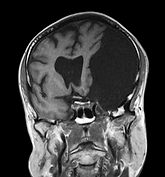

BRAIN TUMOR